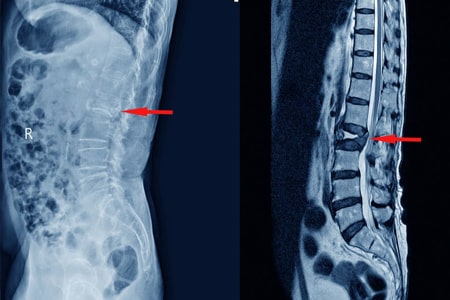

Tratamientos conservadores en el tratamiento de las fracturas vertebrales por compresión con dolor agudo : revisión sistemática y metanálisis en red

23 septiembre 2024

Los AINE y la teriparatida pueden ser las opciones de tratamiento preferidas para el tratamiento del dolor agudo en las fracturas vertebrales por compresión osteoporóticas. Aunque la calcitonina también demostró ser beneficiosa, su perfil de seguridad y los posibles efectos adversos restringen su aplicación generalizada. La evidencia limitada sobre los aparatos ortopédicos y los analgésicos subraya la necesidad urgente de investigaciones futuras. JAMA Netw Open. 3 de septiembre de 2024